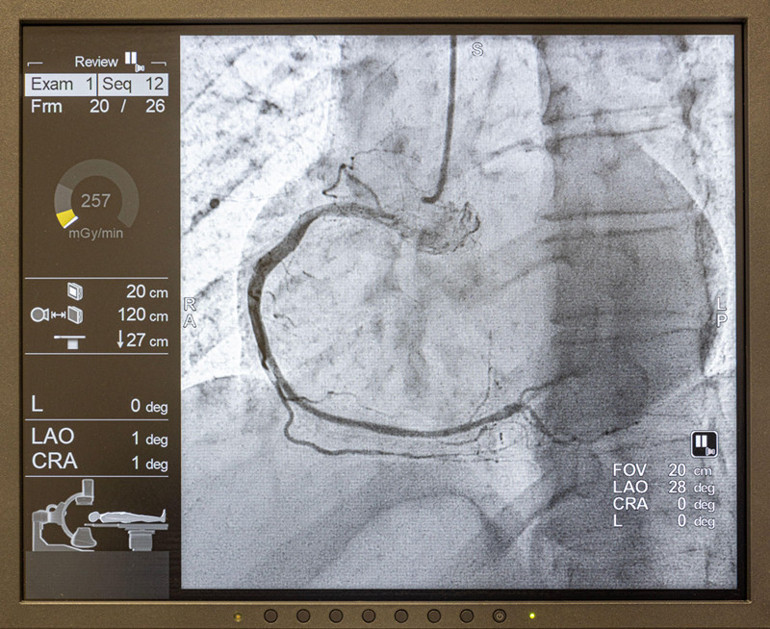

Türk sanat müziğinin efsane ismi Muazzez Abacı, geçtiğimiz haftalarda Amerika’daki evinde kalp krizi geçirmiş, sonrasında anjiyo olmuş ve stent takılmıştı.

Operasyonun ardından yaşanan komplikasyon nedeniyle yoğun bakıma alınan Abacı’nın menajeri Taner Budak, sanatçının son sağlık durumuyla ilgili açıklamasında ‘Anjiyo sırasında verilen kontrastlı sıvının böbreklerinde sorun yarattığını, böbrekleri görevini tam anlamıyla yapamadığı için ciğerlerinin su topladığını, bu sebeple nefes alma sorununun ortaya çıktığını’ söylemişti.

Yapılan bu açıklamalara göre Abacı aslında yaşadığı kalp krizi nedeniyle değil anjiyo esnasında verilen kontrastlı sıvının böbreklere verdiği hasar nedeniyle yoğun bakıma alınmıştı. Usta sanatçının vefat haberi ‘Abacı’nın ölümüne kontrastlı sıvı mı neden oldu?’ sorusunu akıllara getirdi.